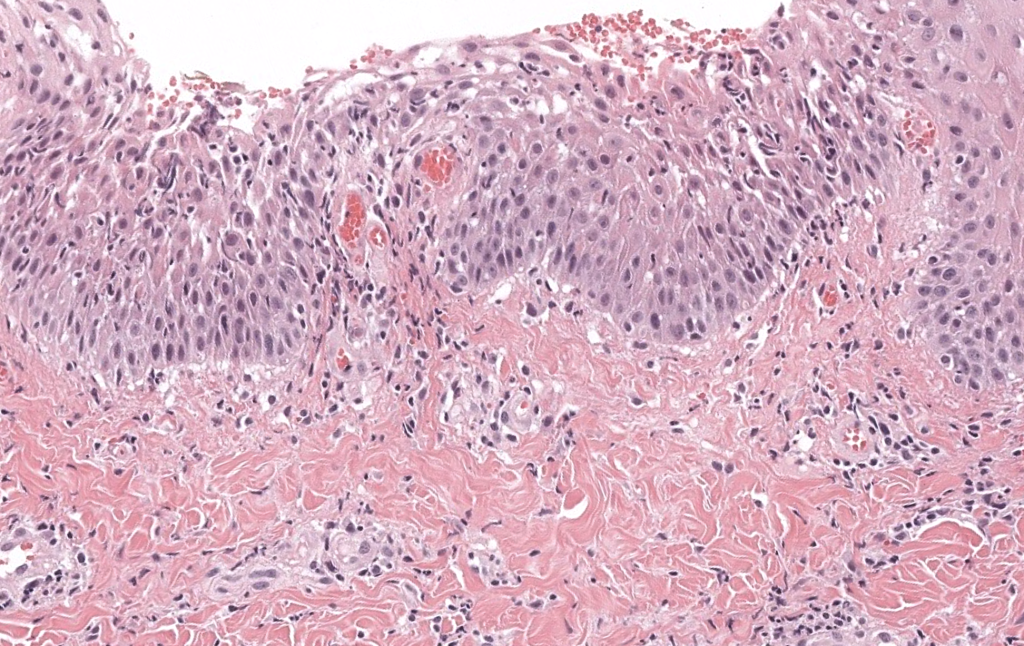

- Histología necesaria

- Biopsia de pústula reciente con gran pústula subcórnea neutrofílica.

- Ausencia de hiperplasia psoriasiforme típica y de vasculitis franca.

- Tinciones especiales negativas para hongos y bacterias significativas.